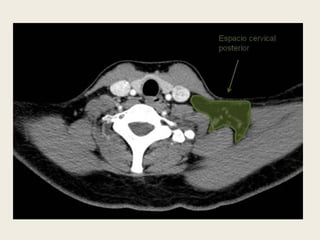

ESPACIO CERVICAL POSTERIOR

 Se localiza en el triángulo

posterior del cuello y se

delimita entre las capas

superficial y profunda de la

fascia cervical profunda,

posteriormente a la vaina

del espacio carotídeo y

anterolateralmente al

espacio perivertebral.

 Contiene grasa, el nervio

espinal accesorio, la cadena

linfática cervical posterior y

el plexo braquial preaxilar.

 El espacio cervical posterior se localiza en el triángulo

posterior del cuello y se delimita entre las capas

superficial y profunda de la fascia cervical profunda,

posteriormente a la vaina del espacio carotídeo y

anterolateralmente al espacio perivertebral.

 Contiene grasa, el nervio espinal accesorio, la cadena

linfática cervical posterior y el plexo braquial

preaxilar.

ESPACIO CERVICAL POSTERIOR Se localiza en el triángulo posterior del cuello y se delimita entre las capas superficial y profunda de la fascia cervical profunda, posteriormente a la vaina del espacio carotídeo y anterolateralmente al espacio perivertebral.  Contiene grasa, el nervio espinal accesorio, la cadena linfática cervical posterior y el plexo braquial preaxilar.

• 51.

 El espaciocervical posterior se localiza en el triángulo posterior del cuello y se delimita entre las capas superficial y profunda de la fascia cervical profunda, posteriormente a la vaina del espacio carotídeo y anterolateralmente al espacio perivertebral.  Contiene grasa, el nervio espinal accesorio, la cadena linfática cervical posterior y el plexo braquial preaxilar.